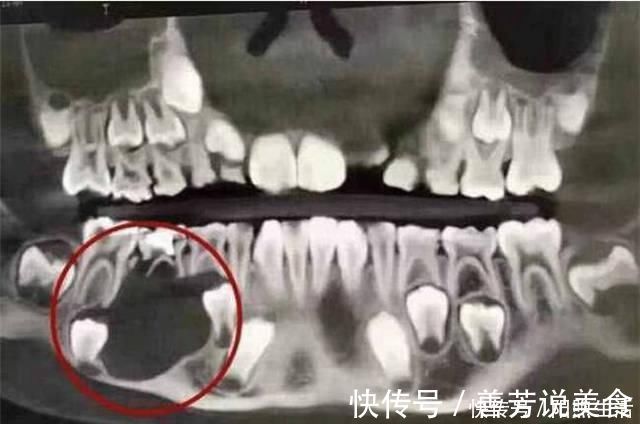

突然有一天小鹏喊牙齿疼,妈妈就想可能是要换牙齿了,所以就打这儿子去医院拔牙。没想到去了医院,医生检查了小鹏的口腔后,顿时就生气了,指责小鹏的妈妈:孩子的牙齿都烂成这样了,怎么现在才带他过来检查牙齿。小鹏妈妈一听也慌了,医生说小鹏的牙齿已经严重被腐蚀,甚至真的牙齿还没长出来就被腐蚀掉了。医生问她原因才知道小鹏的饮食习惯是如此糟糕。

医生说做了那么多年牙医,从没见过那么糟糕的牙齿,现在小鹏的一个牙齿位置已经无法长出新的牙齿, 只能装义齿。拔掉原本牙齿后,医生叮嘱妈妈以后一定要注意孩子的饮食,做到不吃零食,不能喝碳酸饮料,因为碳酸饮料会腐蚀牙釉质,早上起来晚上睡觉一定要刷牙。